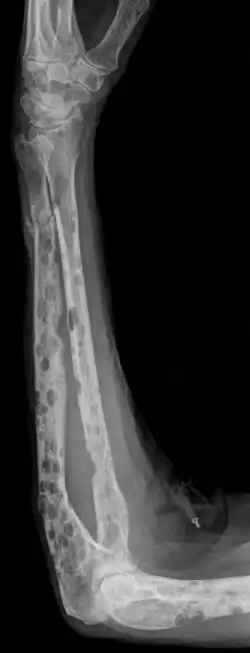

La radiographie du squelette montre très fréquemment des lésions osseuses de type ostéolyse.

La tomodensitométrie à faible dose de tous le corps est plus sensible que la radiographie conventionnelle pour décrire les aspects ostéolytiques ; elle est recommandée depuis 2015 en Europe comme nouvelle norme pour détecter les lésions lytiques du grade 1A du myélome[38].